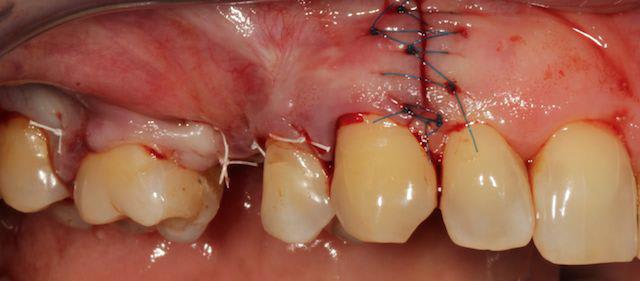

Cas 1-coté gauche maintenant:

photo:

1- ouverture, forme et configuration différente

2- une fois échauffée avec le coté droit, je me dis allez hop, j'attaque une expansion. donc incision crestale avec décharges osseuses

3- mise en place des expanseurs de Mesinger A et B

4-5 notez que l'incision de décharge étant oblique , elle sert également de garde fou contre une éventuelle fracture osseuse. l'os "mobile" vient buter contre l'os "immobile"

la suite en primeur pour ceux qui viennent à Sallanches les 28 et 29 Mars...

Bravo D57 pour ta chirurgie de reconstruction avec le systeme Fast.

mais j'ai quelques remarques:

1. tes vis ne sont pas positionnées comme il faut.

2. tes vis sont trop enfouies

3. tes sutures ne sont pas assez profondes. comme je te le disais à l'ADF, tu dois être à au moins 1 cm de la berge.

4. Donc, je peux te le dire d'avance: le résultat sera moyen. Je t'avais proposé de préparer ensemble le protocole chirrugical. dommmage.